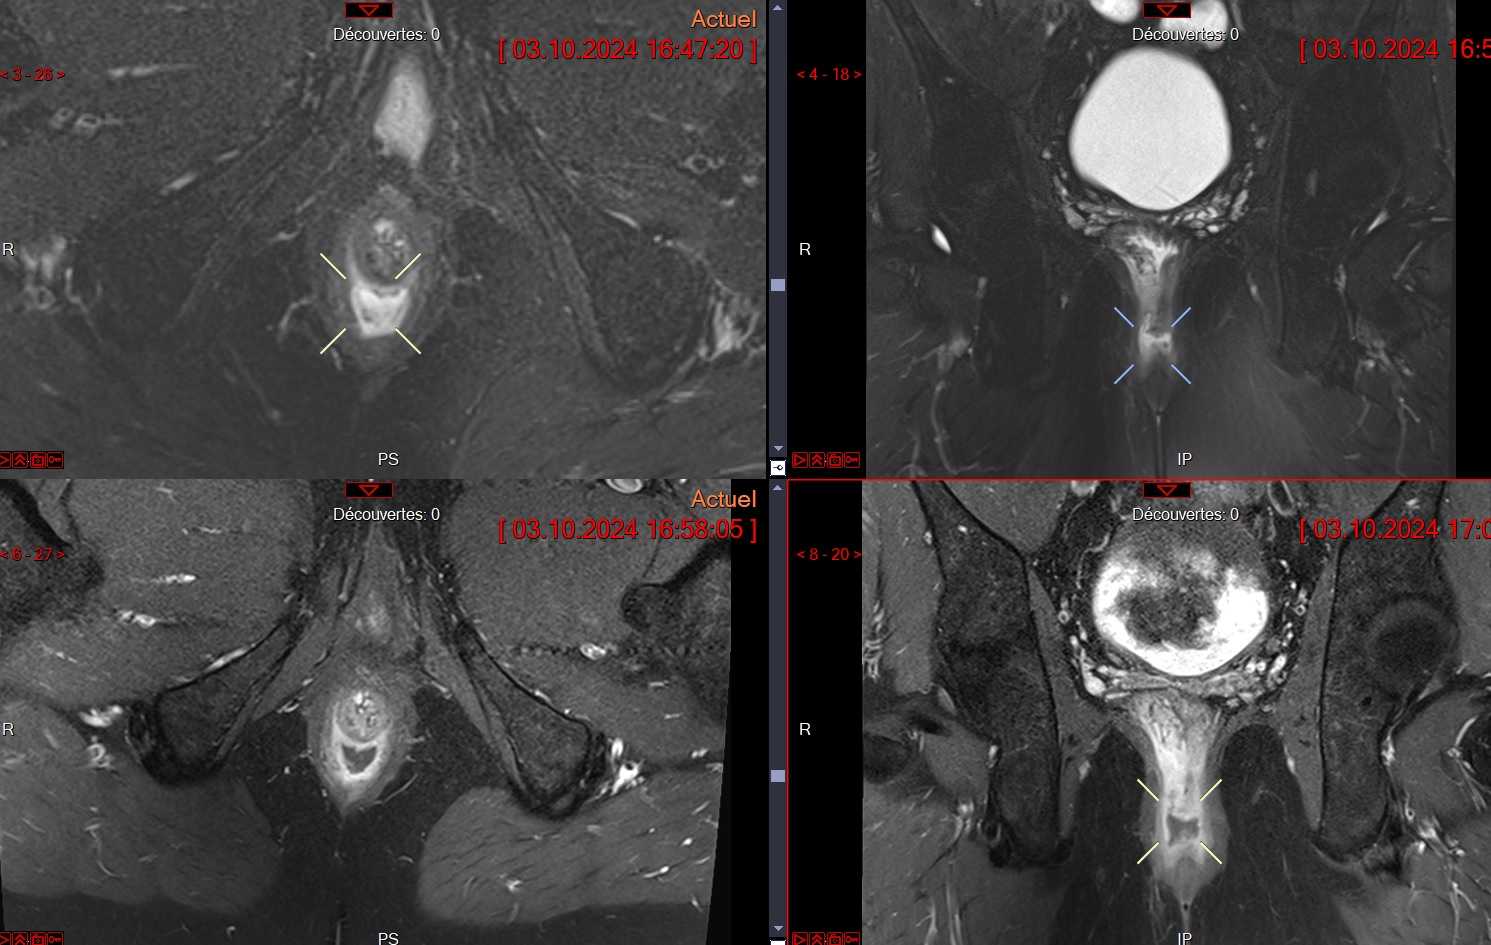

Abcès perianal

Abcès perianal

Abces intersphincterien avec phlegmo local

Abces intersphincterien avec phlegmo local